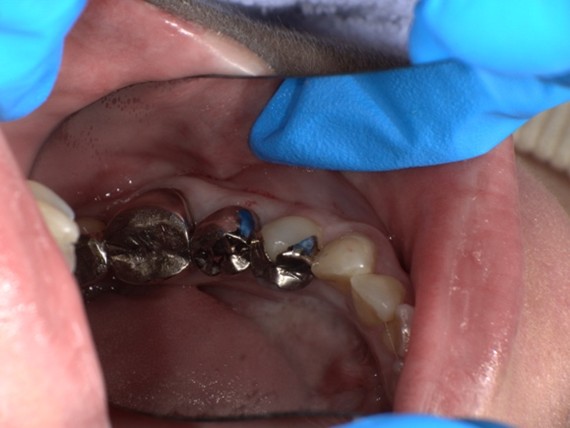

【症例No.4】右上奥歯 セラミックインレー修復/30代女性

Before

After

今回の部位は力が極端にかかる部位ではないため色調の良いガラスの詰め物で製作をしています。透明感がありご自身の歯の色を拾うためとても自然な色合いになるのが特徴です。